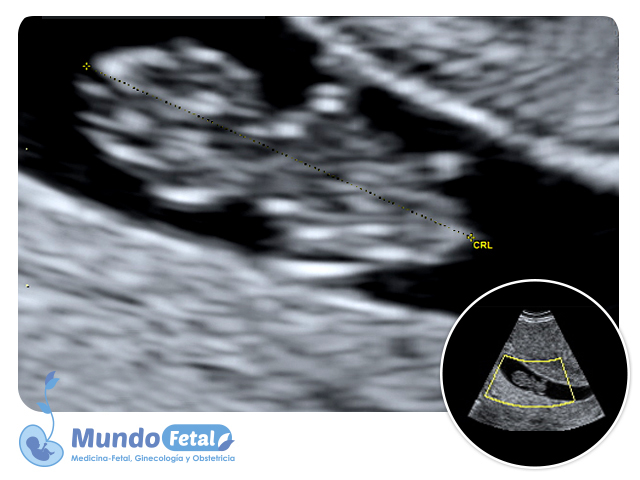

Ultrasonido Temprano 1er Trimestre (Menor 11 Semanas)

Estudio que nos permite la confirmación del embarazo, numero de bebes, valoración de líquido amniótico, placenta, vitalidad por medio de la frecuencia cardiaca, crecimiento armónico y edad gestacional estimada, descartando alguna complicación propia de esta edad.